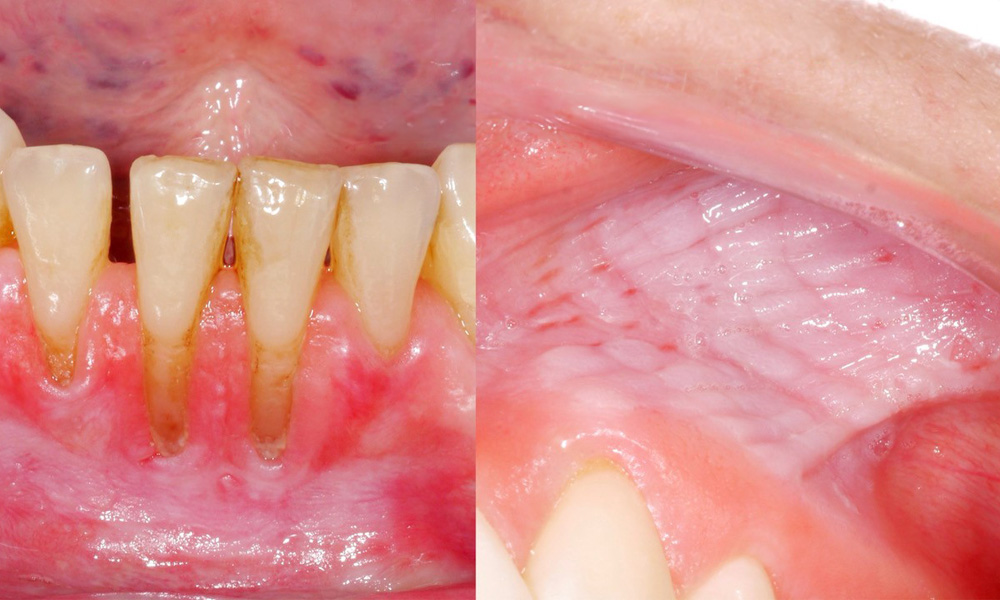

Снусът причинява лезии на лигавицата и гингивални рецесии

Клиничното изследване показа, че редовната консумация на снус може да има следните ефекти върху лигавицата на устната кухина:

- Приблизително 80% от изследваните лица, които са консумирали снус ежедневно, са показали лезии на лигавицата, предизвикани от него.

- За всяка допълнителна кутия снус, консумирана месечно, рискът от по-тежко увреждане на лигавицата се увеличава значително.

- Приблизително 20% от изследваните лица, които са консумирали снус ежедневно, са имали индуцирана гингивална рецесия.

- С всяка следваща година на употреба на снус рискът от индуцирана гингивална рецесия се увеличава значително.